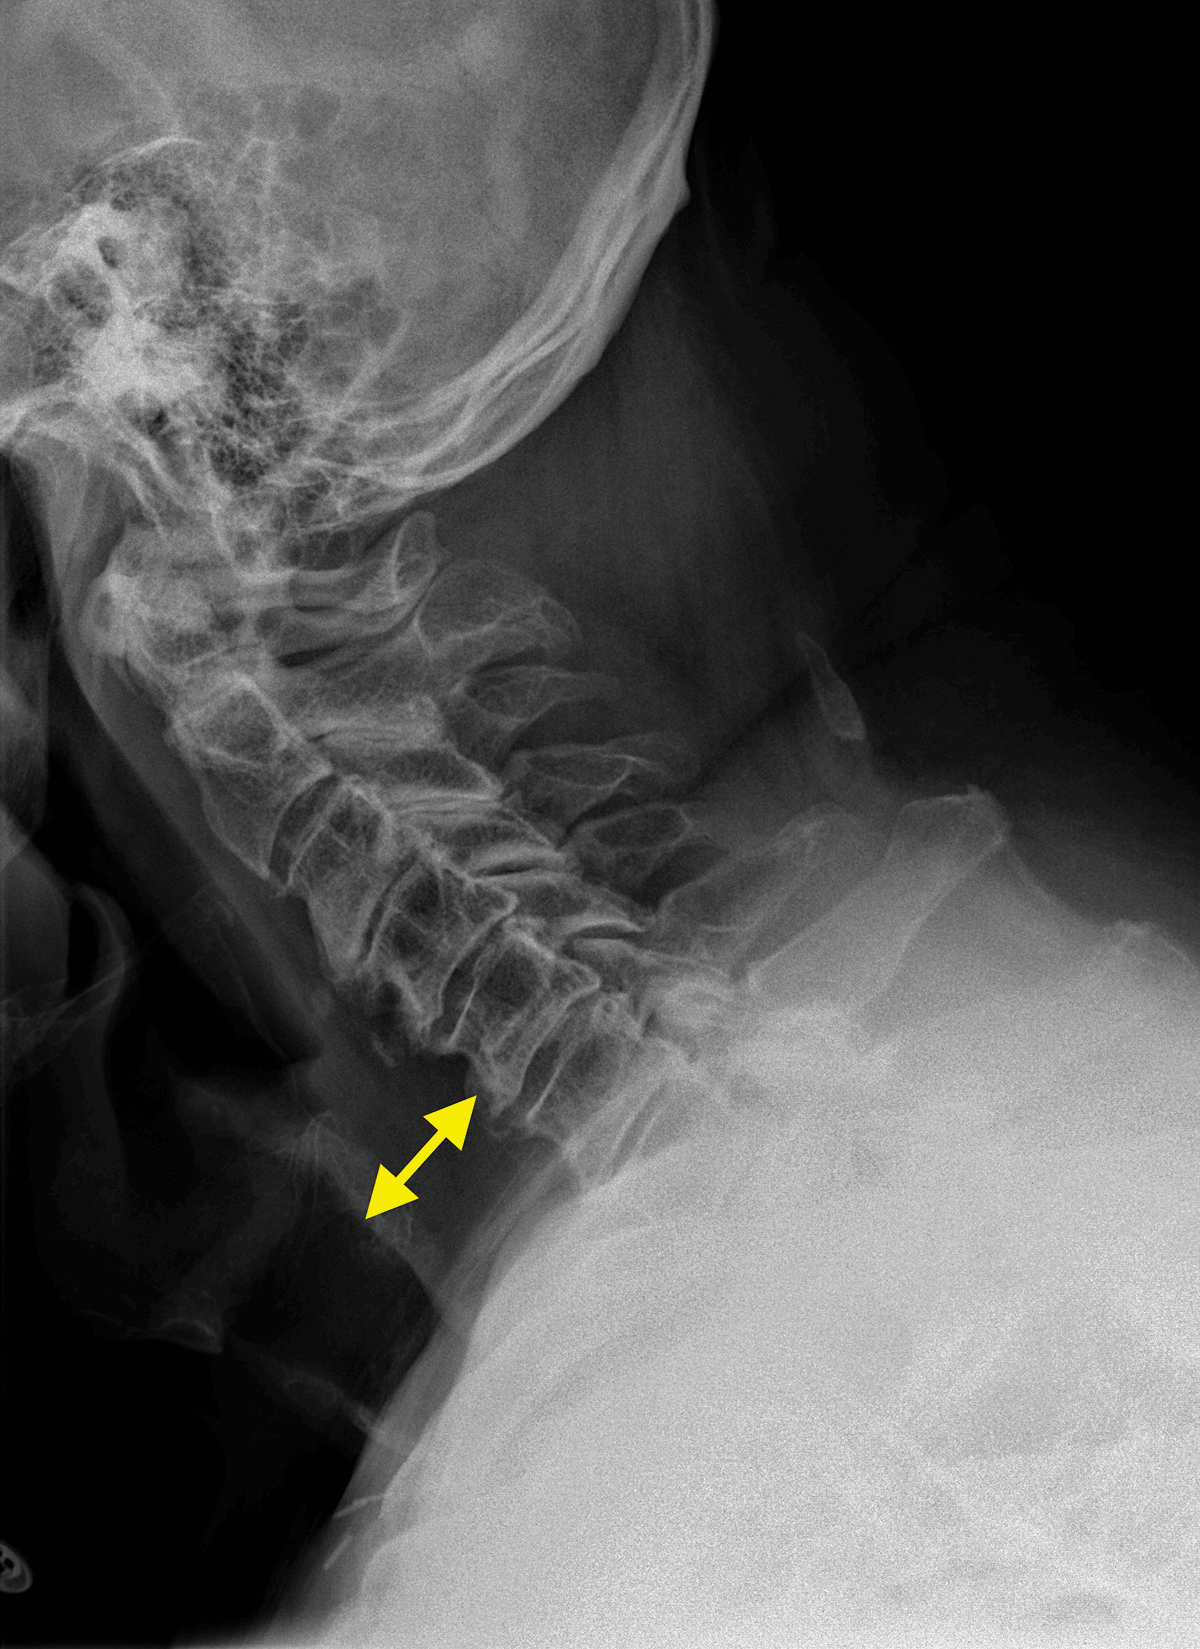

Lateral cervical X-ray showed increased soft tissue thickness of 30 mm in front of C5 (Figure 1, double arrow). Contrast-enhanced computed tomography (CECT) with oral gastrografin administration revealed hematoma extending from the retropharyngeal to the superior mediastinal space without active bleeding or vertebral fracture (Figure 2A, arrows). Axial US image showed a slightly echoic and heterogeneous liquid collection pushing forward trachea and thyroid (Figure 2B).

Figure 1

Lateral cervical X-ray showing soft tissue thickness of 30 mm in front of C5 (double arrow).